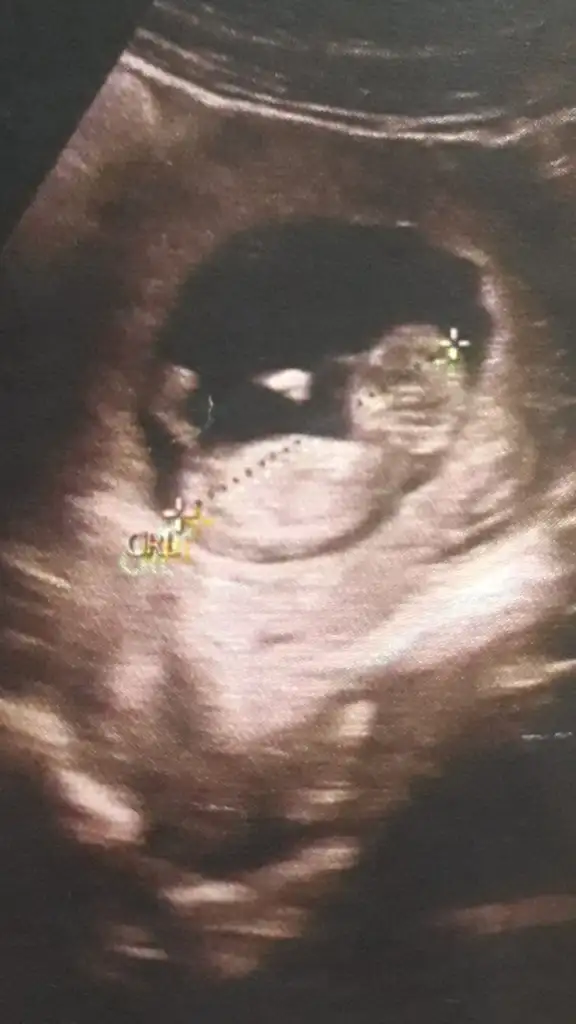

Canım bu 12 artı 4 dü burda doktor kıza benziyor yüzde 80 demişti

• Screenshot_20210114-154037_Gallery.webp

Screenshot_20210114-154037_Gallery.webp

13,6 KB · Görüntüleme: 94